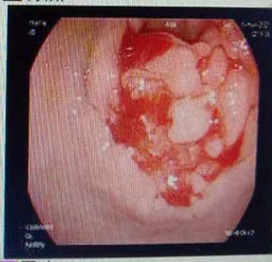

Figure 2: MRI results of upper abdomen (plain scan).

The patient, a 55-year-old male, was admitted to the hospital on March 11, 2021 due to “upper abdominal distension, pain and discomfort for more than 1 year, and recurrence for more than 2 months”. More than 1 year ago, the patient had no obvious inducement of upper abdominal distension, pain and discomfort, no acid reflux, heartburn, no nausea, vomiting, no hemesis, melena, no chest pain, chest tightness and other discomfort, no care, no diagnosis and treatment. Before 2 months, the patient’s symptoms were aggravated again, and the symptoms continued to be not relieved, so the emergency department was admitted to our hospital as “abdominal distension cause check”. Previous healthy, smoking and drinking history, no similar patients in the family. Improve relevant examinations after admission, such as: Infectious disease screening: hepatitis B surface antigen (gold standard method) positive (+), HBVDNA: 3.89 x 106 IU/ml, TAP: 128.03 um², liver function:TP: 50.23 g/L ALB: 27.8 g/L, TBIL: 34.8 g/L, DBIL: 15.00 g/L, IBIL: 19.8 g/L, ALT: 27 g/L, AST: 51 g/L, PCHE: 1879 g/L, AFP: 203.8 ng/ml, Color Doppler ultrasonography of chest and abdomen showed that liver cirrhosis was possible, portal vein velocity decreased, liver disease gallbladder, splenomegaly and splenic vein dilation. 256 row chest and upper abdomen CT (plain scan + enhanced): 1. Ground glass shadow of left lung, follow-up and reexamination are recommended; 2. Liver cirrhosis, splenomegaly, esophagogastric fundus and splenic collateral circulation; The abnormal enhancement focus in the right lobe of the liver, considering the high possibility of liver cancer, the remaining small nodule like enhancement in the liver, considering intrahepatic metastasis (Figure 1). 3. Gastric antrum space occupying, considering malignancy, please combine clinical and pathological findings. 3.0 Mr upper abdomen (plain scan + enhancement): 1. Liver cirrhosis with regenerative nodules, splenomegaly, portal hypertension, ascites and collateral circulation; 2. Abnormal signal of right posterior lobe of liver (Figure 2). Considering malignancy, please combine clinical and AFP examination. Gastroscopy showed: 1. Esophageal gastric fundus varices (severe); 2. Gastric antrum space occupying: Ca? (Figure 3); Gastric antrum pathology (HE staining Figure 4) results: (gastric antrum) adenocarcinoma. Liver puncture pathology (immunohistochemical (Figure 5) diagnosis: (liver puncture) combined with immunohistochemical results, it is consistent with hepatocellular carcinoma. Immunohistochemistry: CerbB2 (0), CK (+), HEPA (partial +), glypican (+), CD (small amount +), CD34 (blood sinus +), CK7 (-), CK8 (+), CK19 (-), CDX2 (-), Ki67 (50% +), GS (+), CK20 (-). Physical examination: Body temperature was 37OC, pulse was 78 beats/ min, respiration was 20 beats/min, blood pressure was 120/70 MHg, skin and mucosa of the whole body were mildly yellow, no rash, bleeding spots, liver palm or spider nevus, superficial lymph nodes were not touched and enlarged, and no obvious abnormalities were found in head, neck, heart and lungs during physical examination. Abdominal distention, soft abdomen, no obvious tenderness, rebound pain and muscle tension in the abdomen, liver, spleen and ribs are not touched, negative mobility dullness, bowel sounds are normal. The patient refused interventional therapy, asked for oral chemotherapy and was discharged after her symptoms improved.